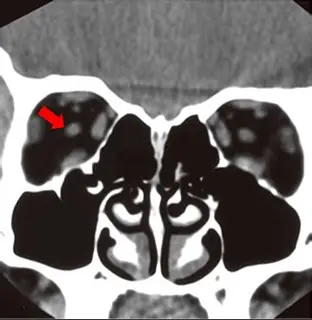

這是一張無打藥的眼眶與副鼻竇冠狀面電腦斷層(Coronal CT)軟組織窗影像。在畫面左側(即病患的右側眼眶)中,可以清楚看到被低密度(黑色)眼眶脂肪(Intraorbital fat)所包圍的各個軟組織結構。我們可由外向內、由上向下依序辨識出形成「肌錐(Muscle cone)」的解剖構造:

- 中央明顯的圓形結構:即為紅色箭頭所指之處,位於肌錐正中心。

- 內側結構:緊鄰內側的篩竇(Ethmoid sinus)與篩板(Lamina papyracea),為內直肌(Medial rectus muscle)。

- 外側結構:貼近眼眶外側壁,為外直肌(Lateral rectus muscle)。

- 上方結構:位於眼眶頂部正下方,為上直肌與提上瞼肌複合體(Superior rectus and levator palpebrae superioris complex)。

- 下方結構:位於眼眶底部上方,為下直肌(Inferior rectus muscle)。

- 內上方較小結構:為上斜肌(Superior oblique muscle)。

- (C) optic nerve(視神經):位於眼眶肌錐正中央,周圍被大量眼眶脂肪包覆,在冠狀面上呈現標準的實心大圓點。紅色箭頭精確地指向此構造,故為正確答案。

根據眼眶的冠狀面 CT 解剖學,上直肌、下直肌、內直肌與外直肌會共同構成一個錐體空間(Cone)。而在這個肌錐正中央,被黑色眼眶脂肪所包圍、且呈現最大最明顯的圓柱狀橫切面構造,必定是視神經(Optic nerve)。紅色箭頭明確標示在此中央圓形構造上,因此正確答案為 (C)。